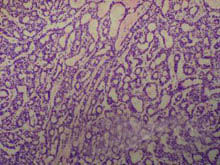

2.鏡檢 由腫瘤性上皮細胞和少量結締組織構成。腫瘤細胞密集成團或呈條索狀,細胞為圓形、卵圓形或梭形,胞漿少,呈嗜鹼性,核圓形、染色深,核仁不明顯。有時上皮團塊的外周部位呈單層排列,頗似皮膚的基底細胞癌,但核分裂象少見。瘤內缺乏肌上皮細胞,腫瘤實質與間質之間界限清楚,有基底膜相隔。有的病例中,上皮團塊內可出現大小不等的囊腔,囊腔內充有變性的腫瘤細胞。間質為纖維結締組織,粘液含量極少。